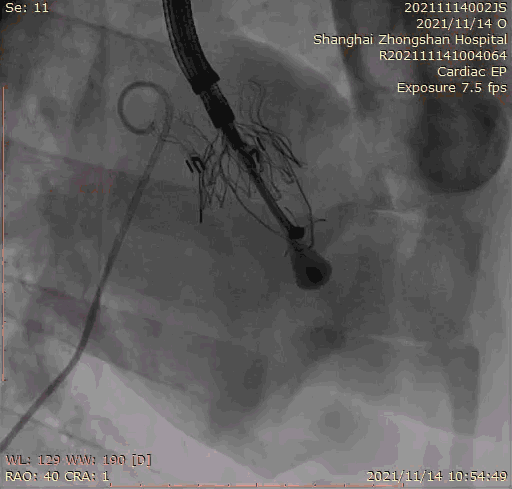

2021年11月14日星期日,复旦大学附属中山医院(以下简称中山医院)葛均波院士团队成功应用经血管介入三尖瓣置换产品Lux-Valve Plus完成临床前研究,并获得圆满成功!此次研究的成功预示经血管三尖瓣产品Lux-Valve Plus已完成临床前准备,即将开启后期的正式临床研究!

上海中山医院葛均波院士、钱菊英院长、周达新教授、潘文志教授、潘翠珍教授、李伟教授共同完成此次临床前研究。术后葛均波院士对Lux-Valve Plus的器械操作性能给予了高度评价,DSA和超声影像也显示出在本次研究中Lux-Valve Plus的安全性和有效性俱佳。

本次临床前研究经右侧颈静脉置入LuX-Valve Plus输送系统可调弯鞘管,在DSA及超声引导下将人工三尖瓣瓣膜植入到原有三尖瓣位置,利用独特的锚定技术将人工瓣膜支架可靠固定在预定的位置。